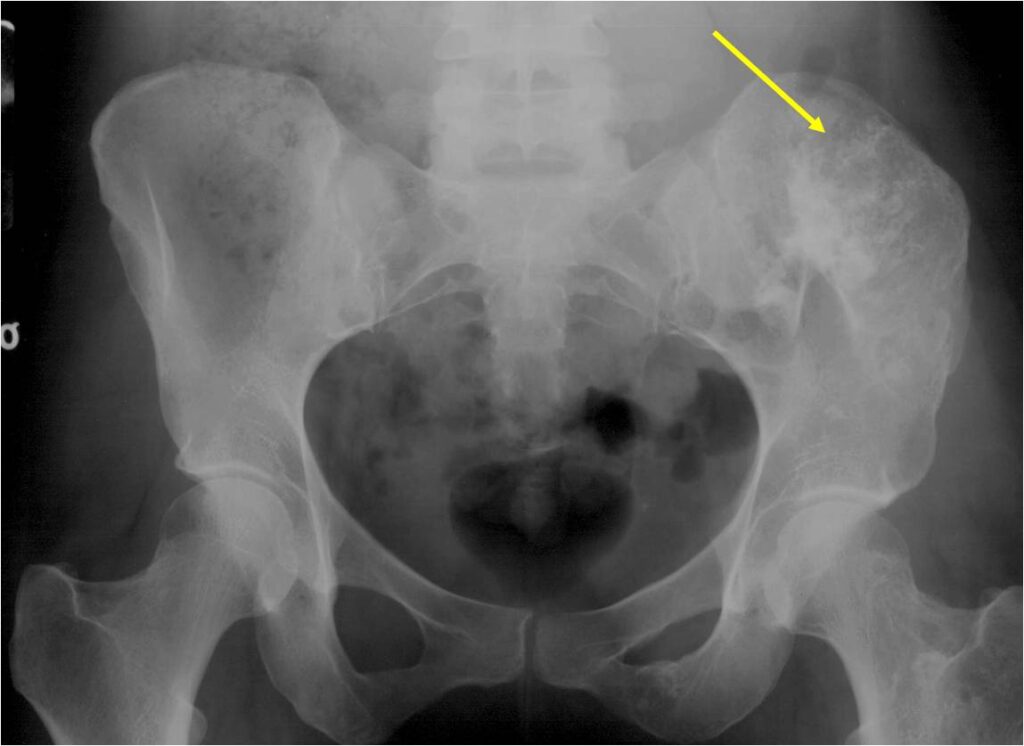

- Enchondromas of the pelvis, vertebrae and ribs are uncommon

- Almost all hyaline cartilage tumors of the pelvis are considered malignant based on anatomic location no matter what the pathology shows. These tumors will ultimately grow locally and have the potential to dedifferentiate or change into a higher grade chondrosarcoma.